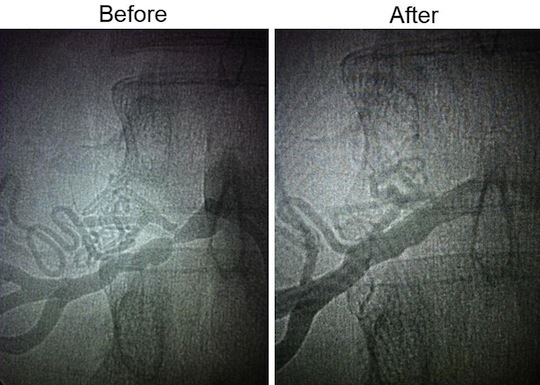

In March of 2012, I finally listened to the one doctor who DIDN’T think my eating habits were unhealthful and got a renal duplex ultrasound. It turned out that I had a relatively unknown disease having NOTHING to do with eating habits called Fibromuscular Dysplasia, which causes arteries to grow like strings of beads instead of tubes. Unfortunately, because so little is known about it, it’s often confused with atherosclerosis (aka plaque). It was easy enough to point out that I had been following the SAD for several years WITH arterial stenosis before adopting this “artery clogging” diet, however.

In June of 2012, I had balloon angioplasty to reopen my nearly closed renal artery. Within minutes of surgery completion, my blood pressure dropped to 117/67.